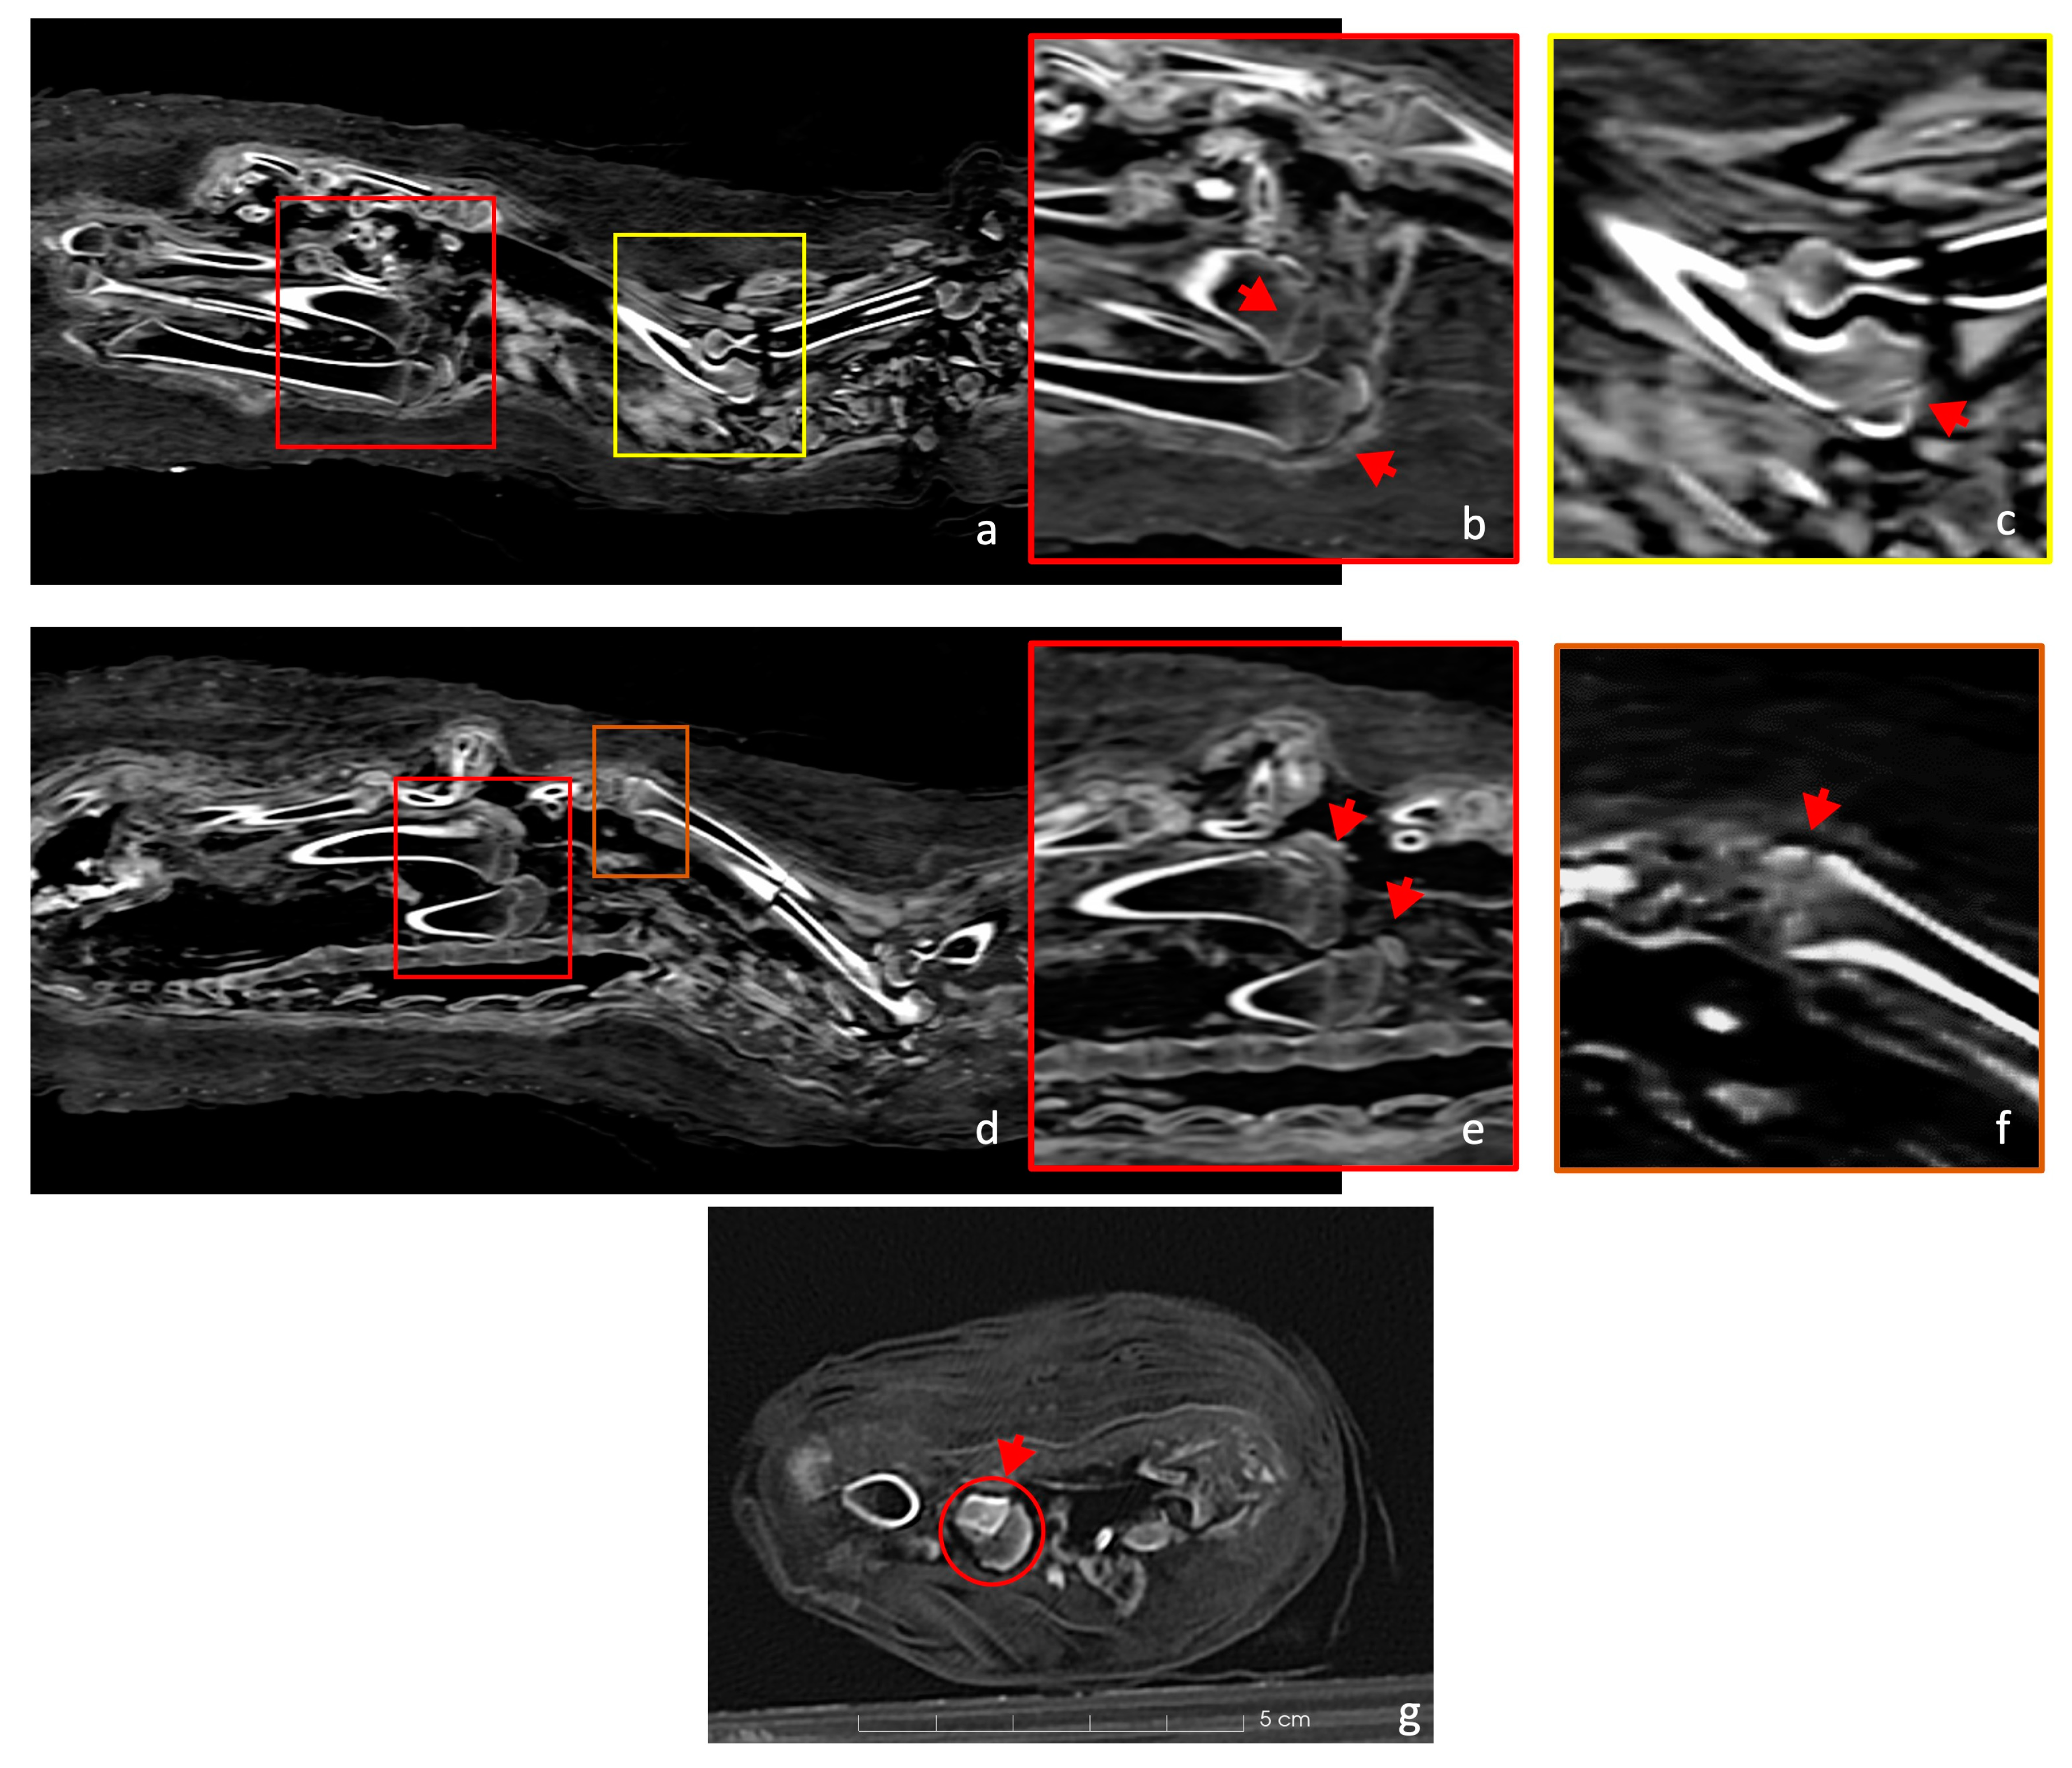

In the hind legs, the femurs’ distal epiphyses were unfused, as were the proximal epiphyses of the tibiae, which appeared to be unfused, with the line between the epiphyses and the shafts being very clear (Figure 4b–e). The proximal epiphysis of the humerus, the ulna, and the distal radius were also not fully developed (Figure 4d,f,g). These provide further evidence of the animal’s age. The epiphyseal status is reported in Table 1.

Figure 4.

(a) The figure presents a coronal view of the right side of the cat’s skeleton. (b) Zooming into the red panel of Figure 4a, it shows the unfused distal epiphysis of the right femur and the proximal epiphysis of the right tibia. (c) Similarly, in the yellow panel, the right proximal ulna physis is open (red arrow). (d) A coronal view of the cat skeleton (left side). (e) Zooming in on the red panel from Figure 4d, this image highlights the unfused distal femoral and proximal tibial epiphyses with a red arrow. (f) Further enlargement (orange panel) within the figure focuses on the incomplete distal epiphysis of the radius. (g) The proximal epiphysis of the right humerus is completely separated.

The scans show that the distal epiphyses of the femurs were unfused, as were the proximal epiphyses of the tibiae (Figure 8). Regarding the forelimbs, the proximal epiphyses of the right humerus and the right ulna were unfused, as well as the distal epiphysis of the right radius. All these findings are an indicator of an immature individual [42,43]. The young age is a problem for its taxonomic identification, as the diagnostic skeletal features are not fully developed and biometry is limited to certain skeletal elements. The distal breadth of the humerus (Bd, following von den Driesch, 1979) is 15.8 mm. The humerus was chosen as the distal epiphyses was already fully ossified. Even if a possible slight further growth of the bone cannot be excluded, the size is in line with the variation of Felis silvestris and looks to be too small for the jungle cat Felis chaus [14]. The size overlaps with that of the sand cat Felis margarita [14], but this species is considered to be much rarer and looks to be uncommon in the zooarcheological record in Egypt [16]. If we hypothesize the attribution to Felis silvestris, common amongst votive mummies [47,48], the individual was almost certainly younger than 9 months [43,44]. Furthermore, the dentition was still composed of deciduous teeth, while the permanent molars were unerupted (Figure 3b) and the fourth premolar of the maxilla was still within the chamber (Figure 3a). Since molars erupt at 5 or 6 months, and the eruption of permanent premolars occurs between 4 and 6 months [45], it is possible to hypothesize that the animal was probably less than about 5 months old at death. This age is very common among cat mummies, as other mummies prove [47,48,50].